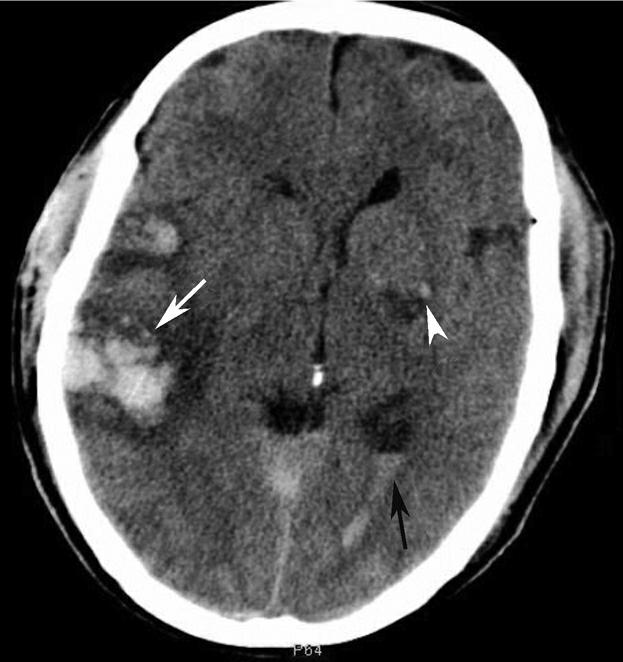

通过病例观察病变情况下的解剖变化(图1-2-87~图1-2-114)。

图1-2-87 脑挫裂伤并脑室内积血

右侧颞叶(白箭)、左侧基底节区(白箭头)大片状高、低混杂密度影。左侧侧脑室后角积血(黑箭)